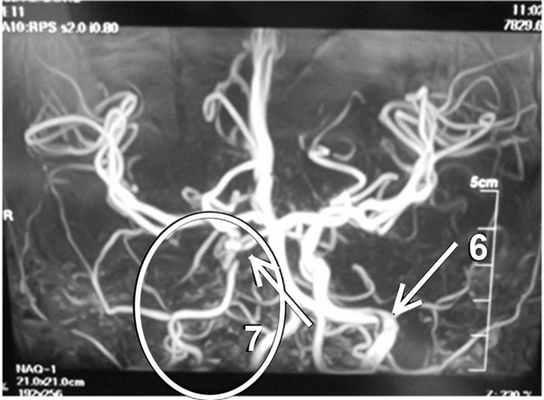

Наложены вторичные швы на заушные раны 16.10.14. В левую барабанную перепонку вставлен шунт, так как в барабанной полости скопился прозрачный экссудат. 25.10.14 проведена МРТ головного мозга, на которой выявлено сужение правой внутренней сонной артерии до 3 мм. На уровне вхождения в кавернозный синус на протяжении 10 мм кровоток не визуализируется (рис. 2). При контрольном осмотре через 1,5 мес самочувствие ребенка хорошее. В заушной области с обеих сторон линейный рубец. Из левого уха удален шунт, барабанная перепонка серая, опознавательные знаки есть, слух субъективно в норме. В правом ухе полость полностью эпидермизирована, сухая, шепотная речь 1—2 м.

Рис. 2. МРТ головного мозга в ангиорежиме от 25.10.14. 6 — левая нормальная внутренняя сонная артерия. Овальной линией выделено сужение правой внутренней сонной артерии; 7 — участок облитерации правой внутренней сонной артерии.